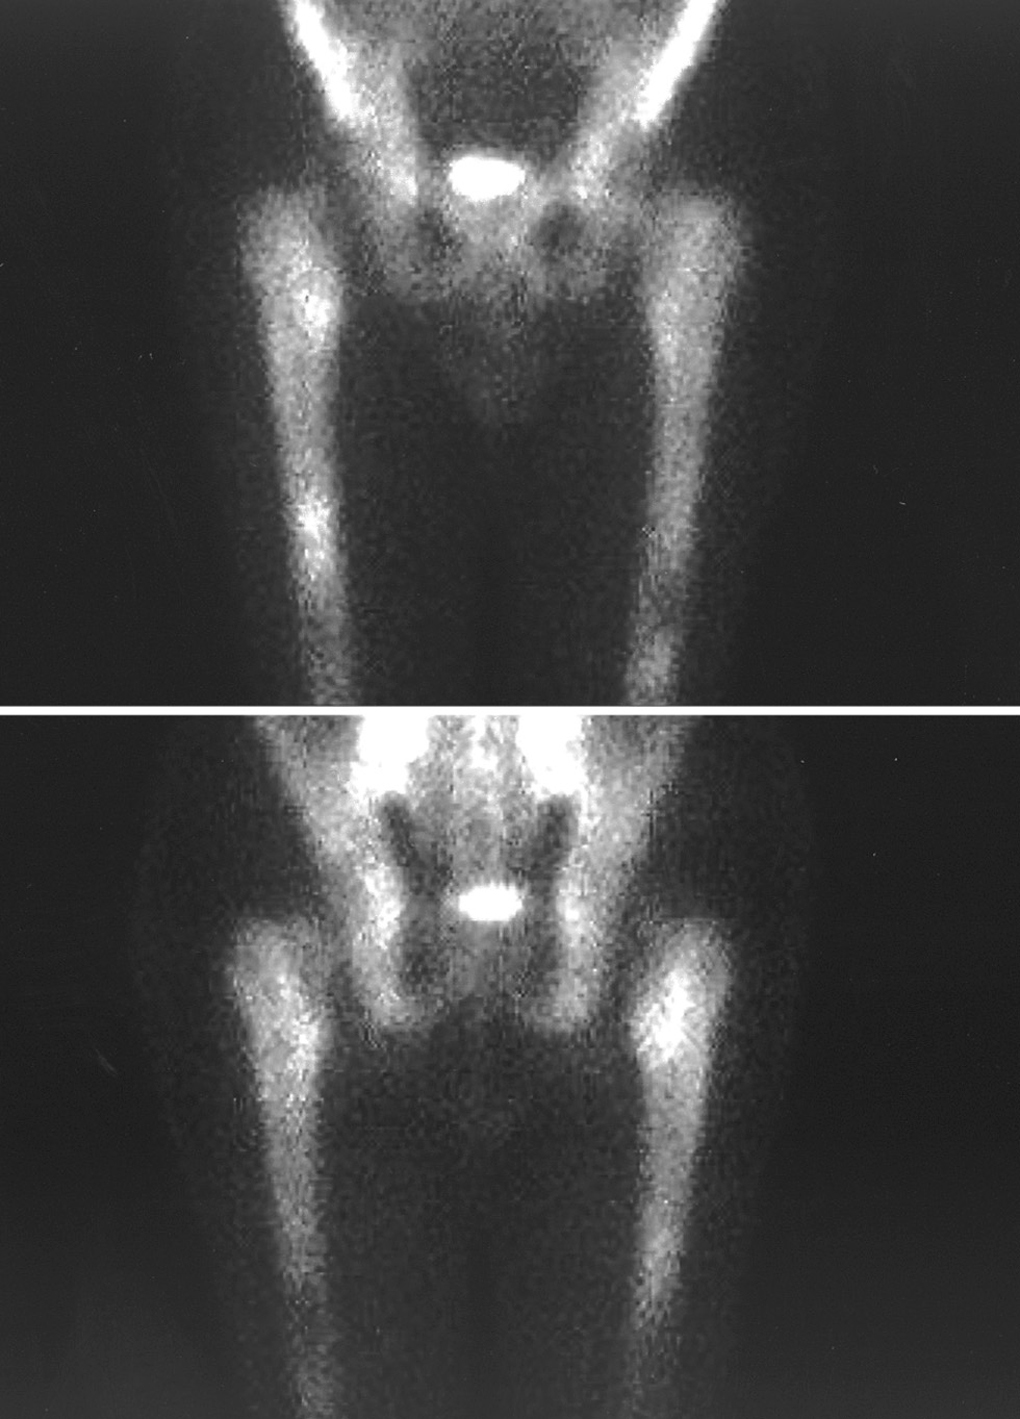

Presentamos el caso de un varón de 43 años, que ingresa con el diagnóstico de enfermedad de Still, tras varios meses aquejado de artralgias, febrícula y pérdida de peso. Se realizan radiografía de tórax, ecografía abdominal, TC de tórax, abdomen y pelvis con contraste y gammagrafía ósea. Los hallazgos gammagráficos orientan hacia la realización de punción de médula ósea con el diagnóstico de leucemia linfoblástica aguda.

We present a 43-year-old male, who was admitted with the diagnosis of Adult-onset Still's disease, after several months of arthralgias, febricula and loss of weight. Chest x-ray, abdominal ultrasonography, chest, abdomen and pelvic CT scan and bone scintigraphy were performed. Scintigraphic findings oriented to the performance of a bone marrow biopsy with diagnosis of acute lymphoblastic leukemia.